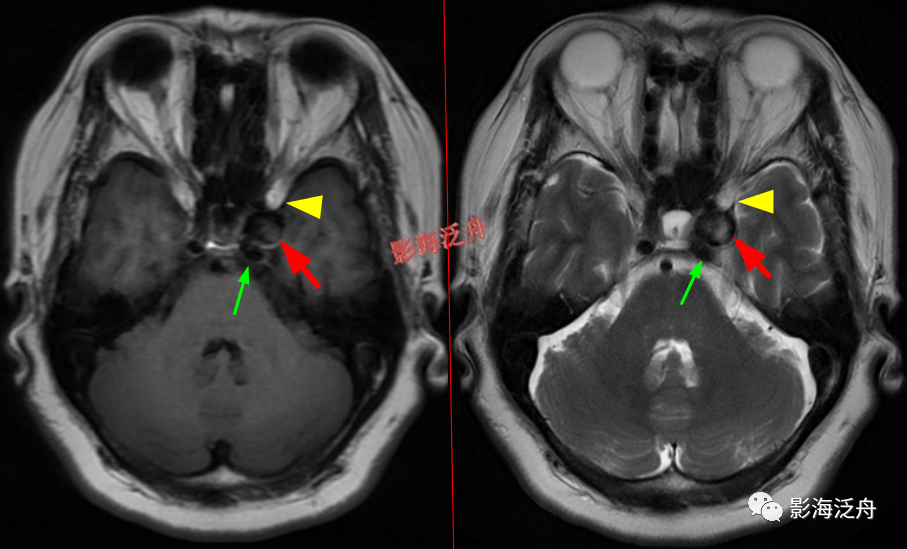

海绵窦、CPA区病变

左侧颈内动脉海绵窦段动脉瘤

伴血栓形成(红箭),绿箭为海绵窦段起始端,黄箭头所指为颈内动脉分段的重要解剖标志——前床突(颈内动脉分段可参考之前的文章 颈内动脉CTA分段(超实用))。

海绵窦周围除了动脉瘤外,占位性病变也比较常见,如脑膜瘤、神经鞘瘤、脑外海绵状血管瘤

等。

脑膜炎

患者,桥前池内可见异常增多的血管影(红箭),正常人的桥前池因为脑脊液流动产生的伪影也可以看到池内絮状低信号(绿箭),但不如右侧患者的明显,这个观察起来比较困难,就如在腹部CT

上观察患者是否存在肝脏肿大一样,需要一个经验积累的过程。黄

箭指基底动脉,蓝箭指三叉神经。